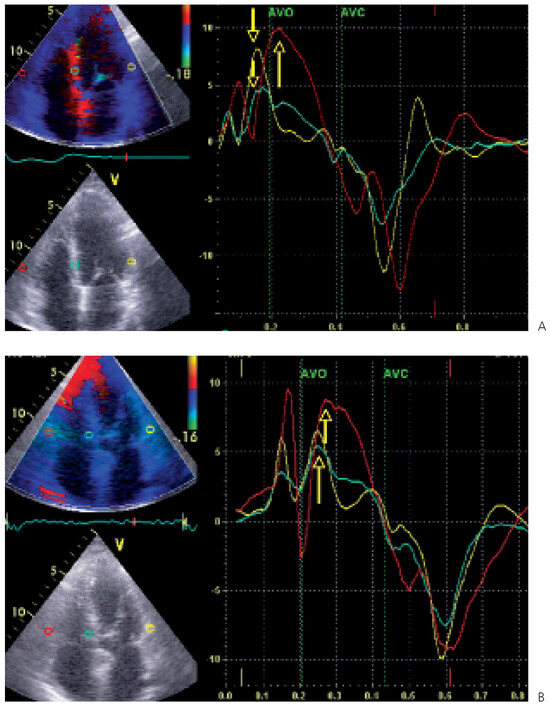

While substantial progress has been made over the past decade in the medical treatment of heart failure, certain patients fail to respond to optimal treatment despite the availability of excellent drugs. Cardiac resynchronisation therapy, or multisit...